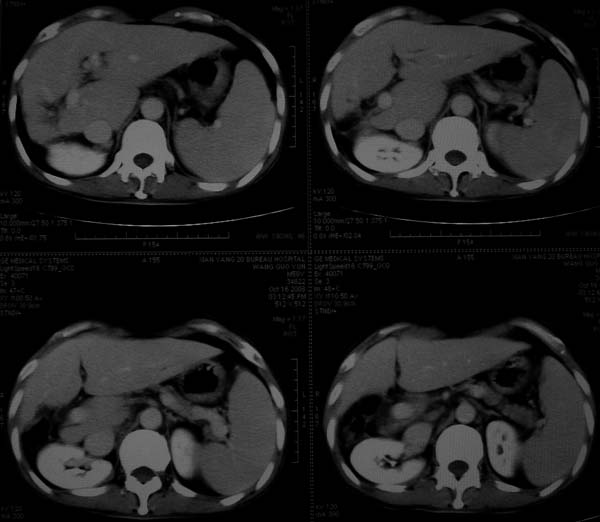

标题: CT16292:男,53岁,上腹部不适2月,B超发现肝内占位病变。 [打印本页]

标题: CT16292:男,53岁,上腹部不适2月,B超发现肝内占位病变。

符合肝ca增强,\"快进快出\";肝叶比例失常,右叶萎缩,肝裂增宽,脾大,肝硬化可能.

肝硬化,多结节肝癌。比较典型的表现了。

肝叶比例失调,左叶增大,肝裂增宽,脾脏增大,门脉增宽,肝右叶包膜下多发结节样阴影,增强虽说强化幅度不大,但还是符合快进快出特点;考虑肝硬化、脾大、结节型肝癌。胆管细胞癌多有延时强化、肝包膜凹陷征、周围胆管扩张等特点,本例明显不符;故不考虑。

支持结节型肝癌 肝硬化 脾大

动脉期静脉有显影 是否静脉有受侵改变啊